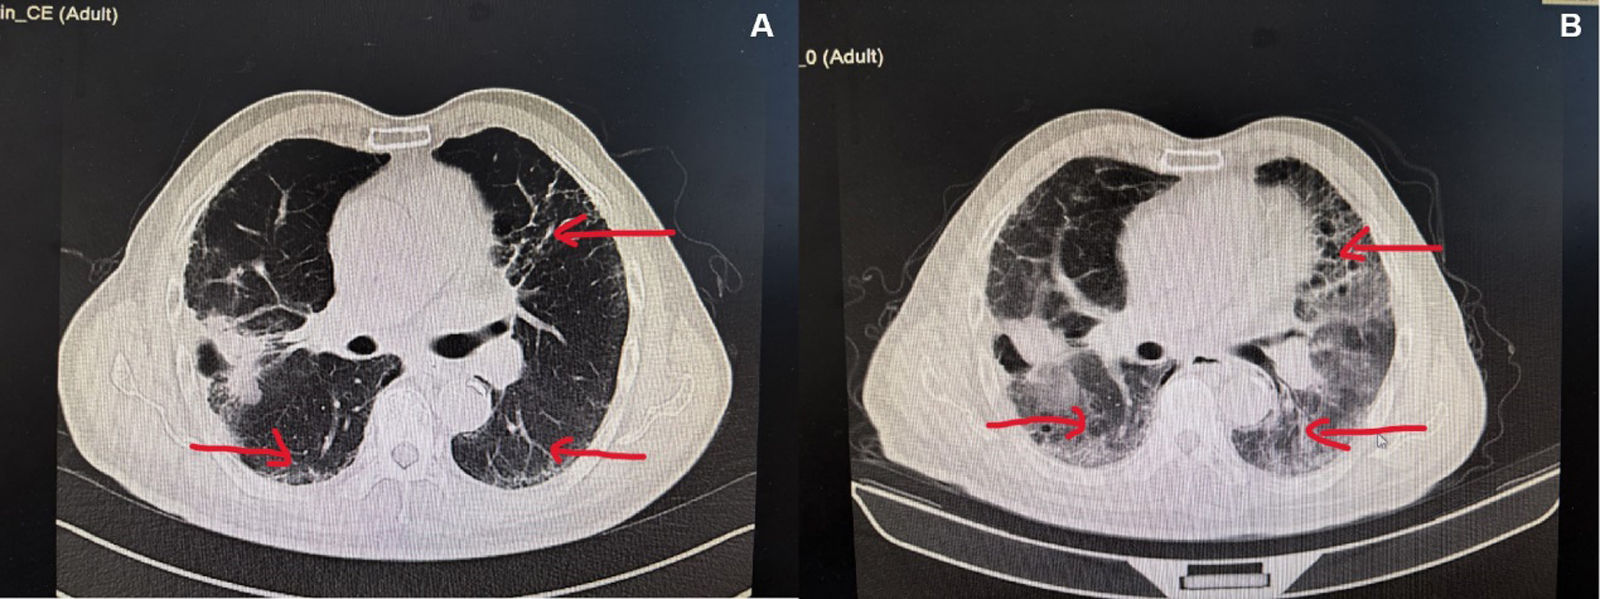

Lung fibrosis secondary to sintilimab

Fibrosis pulmonar secundaria a sintilimab

Qiu-Hong Sun, Ye Hu, Shi-Hui Li

Department of Oncology, Beijing Electric Power Hospital of State Grid Co. of China, Capital Medical University Electric Teaching Hospital, 100073 Beijing, China